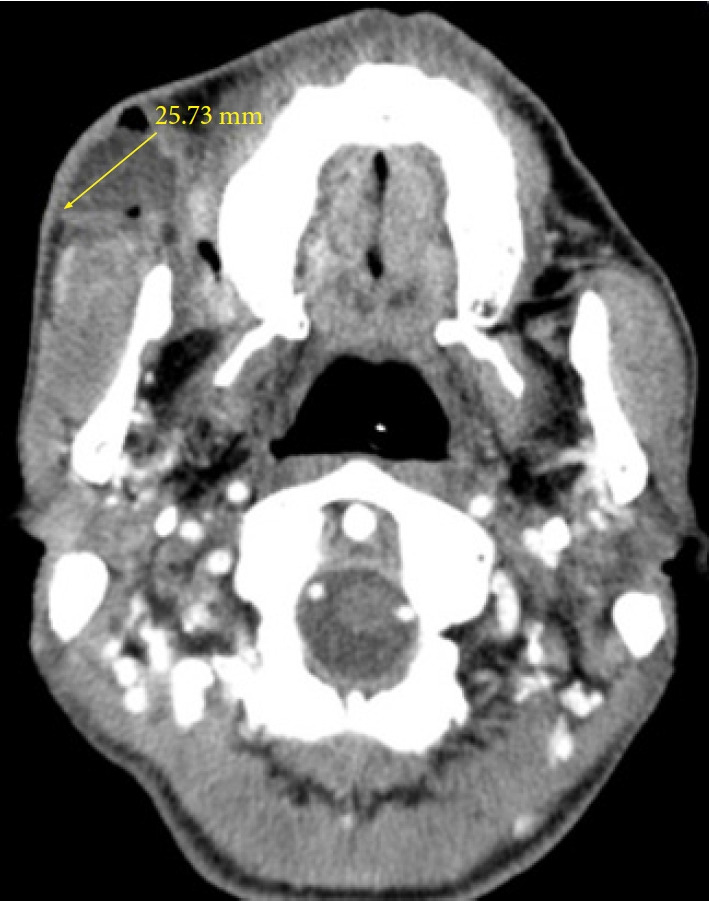

Recurrent parotid sialocele is rare and challenging to treat. Treatment options are limited for cases of parotid sialocele that recur despite ductal ligation. This case study presents a patient who underwent wide excision of the right buccal mucosa due to squamous cell carcinoma. During the wide excision, a segment of the parotid duct was excised, and ductal ligation was performed to prevent the occurrence of a sialocele, followed by reconstruction using a folded anterolateral thigh free flap. Twenty-two days after surgery, parotid sialocele occurred despite the initial ductal ligation and subsequent ductal ligation was performed; however, the sialocele recurred. As an alternative therapeutic option, a transdermal scopolamine patch was applied for 3 weeks, with one patch used every 3 days. The results were encouraging, with complete resolution of the sialocele. A transdermal scopolamine offers a noninvasive, convenient method of treating parotid sialocele with minimal side effects. The successful outcome of this case suggests that a transdermal scopolamine can be an effective therapeutic option for recurrent parotid sialocele in conjunction with surgical treatment.